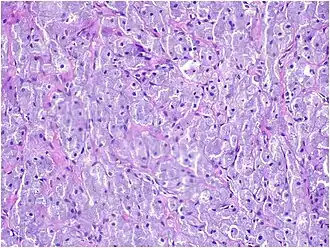

A low-power microscopic image reveals stratified squamous epithelium with a subepithelial proliferation of large polygonal cells arranged in nests and dense sheet [7]

A medium-power microscopic view displays nests and sheets of large polygonal cells with abundant granular eosinophilic cytoplasm and a centrally located nucleus [7]

A high-power microscopic view reveals variably sized blood vessels scattered throughout certain areas of the lesion [7]

Histopathologically, congenital epulis is usually characterized by the presence of big, rounded cells that fill the mucosa's lamina propria and have round to oval nuclei and an abundance of eosinophilic cytoplasm.[10] A thin layer of connective tissue separated the surface layer of cells from the growing new cells. Numerous histological traits, such as a fibrous and granulomatous appearance, have been reported in recent research.[10]

Microscopically, congenital epulis is composed of:

• Sheets of proliferating polygonal to round cells with overlying thin squamous, eosinophilic, granular cytoplasm[12][13]

• Centrally located, round nuclei [7]